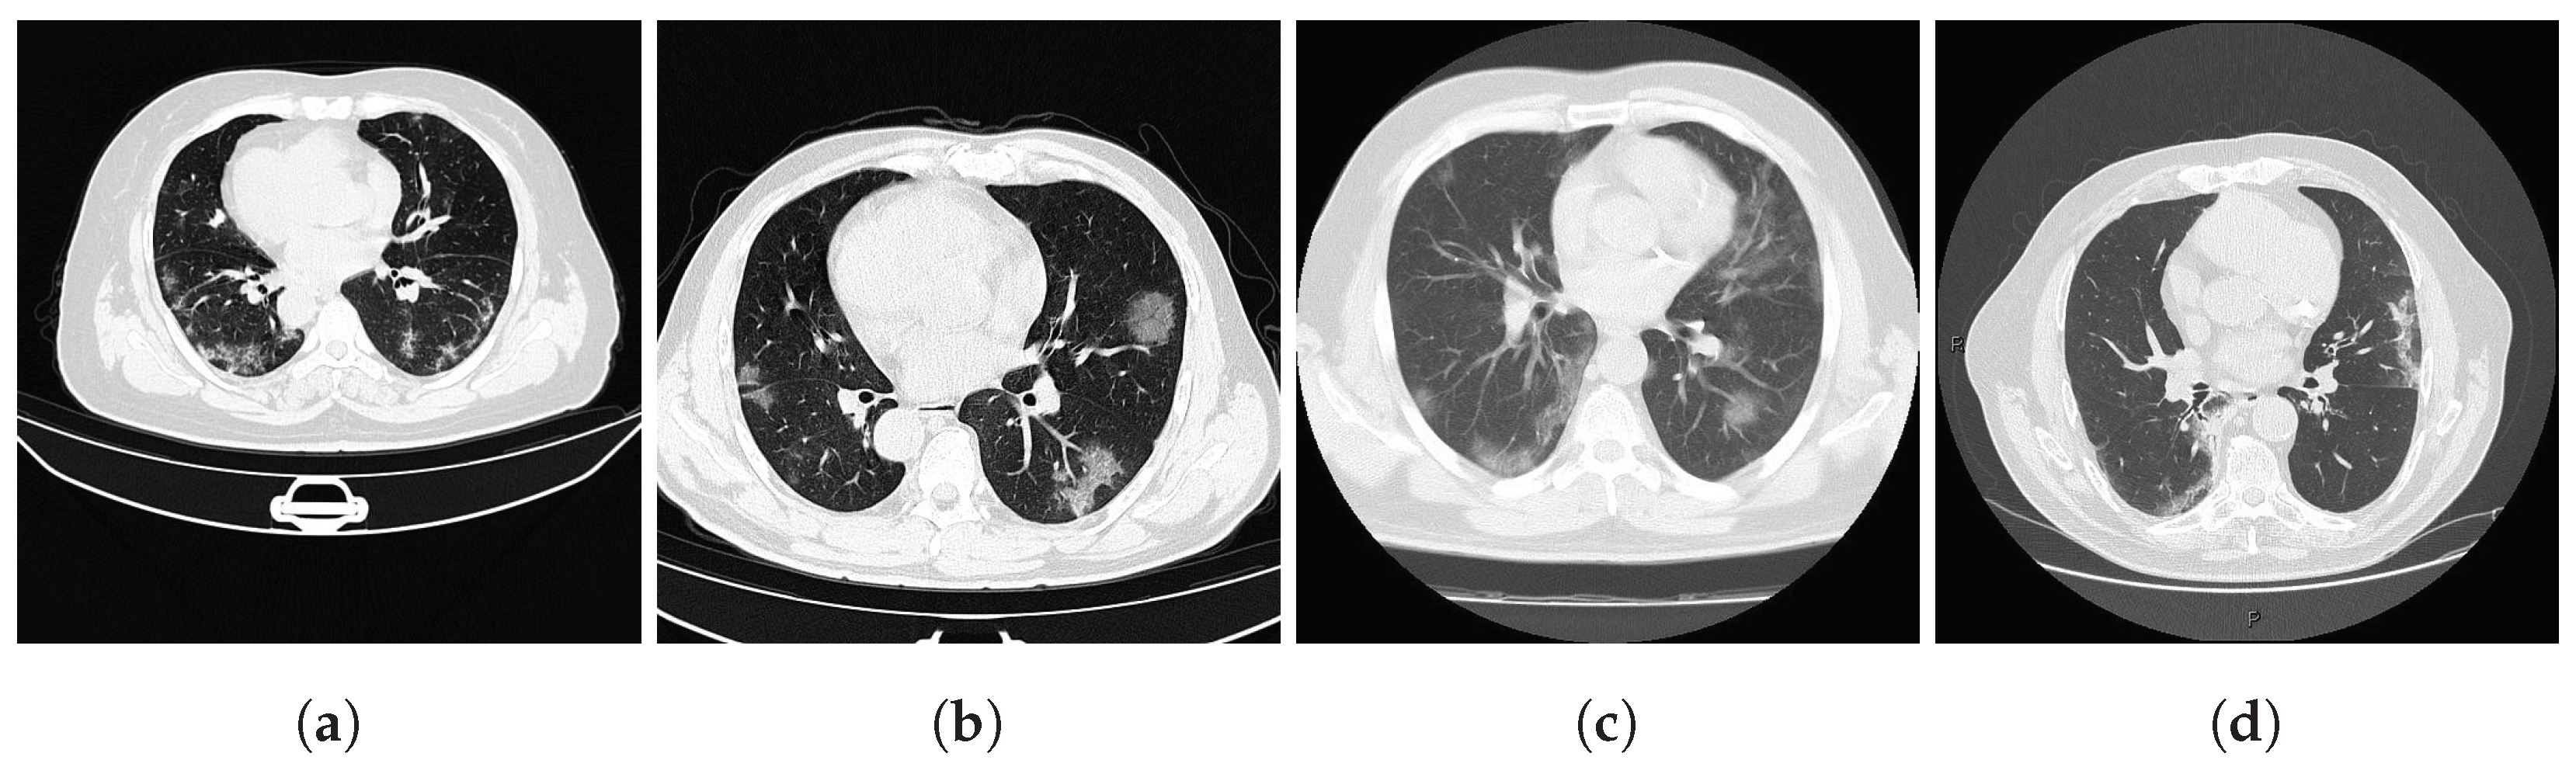

To assess SAM 2’s performance in segmenting medical images, compare it with the original SAM, and test our proposed approach to medical image segmentation, we selected two widely recognized public lung datasets, one comprising axial lung scans and the other containing frontal chest X-rays, ensuring representation of both image modalities in our experiments. These datasets were chosen due to their accessibility, publication status, and frequent use in previous scientific studies, underscoring their significance in comparative research. Furthermore, they are the same datasets used in our previous work [9], allowing for a direct comparison between the models. Image dimensions are described in width × height.

Both datasets provide lung masks verified by radiology specialists, ensuring the availability of well-labeled data for research. The first dataset (COVID-19) includes 20 axial lung scans [18], divided into two subsets: Coronacases (see Figure 1a) and Radiopaedia (see Figure 1b). The quality of the CT slices in the Coronacases subset is superior to that of the Radiopaedia subset, the latter being composed of cone beam CTs with lower resolution, hence the disparity in quality. Moreover, while the Coronacases subset consists exclusively of 512 px × 512 px slices, the Radiopaedia subset is more varied, including 829,630 px × 630 px slices and 110,630 px × 401 px slices. Coronacase CT scans in this dataset average 258.1 slices, while Radiopaedia averages 93.9 , providing 3520 slices for evaluating SAM 2’s performance. This dataset is also utilized to evaluate the performance of DMDF-Net, as reported by Owais et al. [19]. The differences between these two kinds of CT make them ideal for a separate study so that they will be treated as different datasets during this work.

The second dataset (Montgomery) comprises 138 frontal chest X-rays [20], provided in Portable Network Graphics (PNG) format, along with corresponding left and right lung masks (see Figure 1c). Chen et al. [21] used this dataset, referred to as Montgomery after the collection site in Montgomery County, MD, USA, to evaluate the performance of TransAttUnet. This dataset contains 414,892 px × 4020 px slices and 4020 px × 4892 px  slices.

In this study, the selected prompting approach combines minimal point coordinates within a bounding box. This method is intended to simulate an interactive tool where a specialist might begin by drawing a bounding box around the lungs, then marking the areas to be segmented (i.e., the lungs), and finally, indicating parts of the background to be excluded. Figure 1 illustrates two examples of this approach using different CT slices: one from each subset of the selected dataset (Coronacases and Radiopaedia) and a chest X-ray. The orange box encompasses all the masks generated for the current slice. The green circles denote a point near the center of each lung. In contrast, the red circle identifies the background, indicating a region that should not be considered part of the lungs.